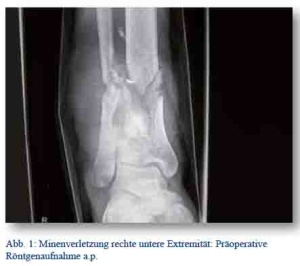

Die radiologische Diagnostik, inklusive CT, zeigte eine Fraktur des Sitz- und Schambeines mit Azetabulumbeteiligung (Abb. 1 und 2). Es stellte sich weiterhin eine Einblutung in die umgebenden Weichteile, in die Mm. iliacus und obturatorius sowie ins Becken dar (Abb. 3).

Am Unfalltag wurde die offene Oberschenkelfraktur links mittels Fixateur externe versorgt (Abb. 6 und 7). Bei stabilen Kreislaufparametern wurde der Patient auf der Intensivstation weiter behandelt und mit einer über die Dauer der operative Versorgung hinausgehenden Beatmung versorgt. Diese war vor allem durch die erschwerte Oxygenierung infolge der Lungenkontusion erforderlich. Die Gesichtsschädelverletzungen konnten konservativ behandelt werden.